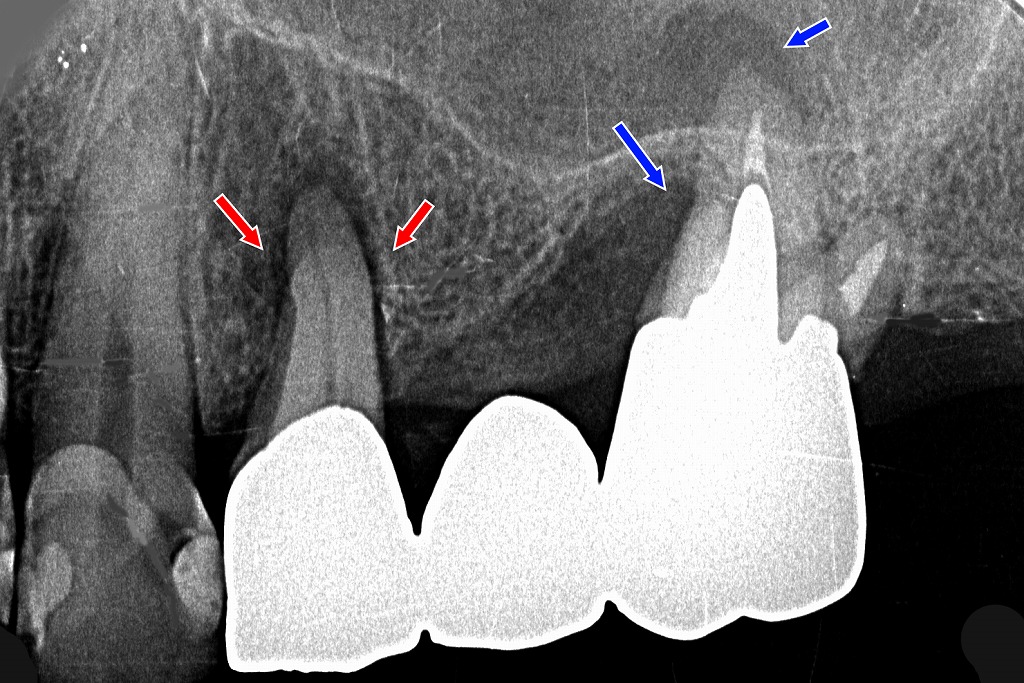

このX線画像は 上顎4番・5番・6番がブリッジで連結されている症例 で、

特に 4番(前方の支台歯)に強い負担が集中し、咬合性外傷が起きている状態 が示唆されます。

① 上顎4番:咬合性外傷による変化

(赤矢印部)

● 歯根膜腔の拡大

4番の根の周囲に 歯根膜腔の明らかな拡大 が見られます。

これは以下のような 咬合性外傷の典型所見 です:

- かみ合わせの力が過剰にかかっている

- ブリッジの荷重が前方の4番に偏っている

- 6番の支持力低下を4番が補ってしまっている

● 動揺の可能性

歯根膜腔の不均一な拡大は 歯のぐらつき(動揺) と関連しており、

長期間続くと歯周組織の破壊がさらに進行します。

② 上顎6番:重度の歯周病による骨吸収

(青矢印部)

● 骨の支持が大きく失われている

6番の歯根周囲の骨が大きく吸収しており、歯周病が進行しています。

歯根長の 1/2 以上に及ぶ骨吸収も見られ、支台歯としての支持力が弱い状態。

● 根尖病巣も認められる

6番の根尖部には、暗い透過像=根尖病巣(根の先の炎症) があり、

歯周病と根尖性病変の複合型が疑われます。

③ ブリッジ全体の力学的問題

● 6番の支持力が低下

骨吸収+根尖病巣+動揺により、6番は本来の支台歯としての役割を果たしにくくなっています。

● 結果として4番に負担が集中

6番の支持力低下を補おうと、

4番が過重負担を受け、歯根膜腔拡大(咬合性外傷)を起こしている状態です。

● 4番の歯周組織にも悪影響

負担過重が続くと、

- 歯槽骨の吸収

- 歯根膜の破壊

- 動揺の悪化

が進み、長期的には 支台歯の喪失リスク が高くなります。

④ 外傷性咬合の典型サイン(本症例に一致)

- 歯根膜腔の不均一な拡大(特に4番)

- 歯槽骨の縦方向の吸収

- 支台歯の動揺

- 咬合力の逃げ場がないブリッジ構造

- 歯周病+根尖病巣で支台歯の支持が弱い

これらが複合的に起きると、

ブリッジ全体が不安定になり、負のスパイラルに陥ります。

咬合調整、6番の治療(根管治療・歯周病治療)、ブリッジ再設計(分割含む)などが検討されるケースです。